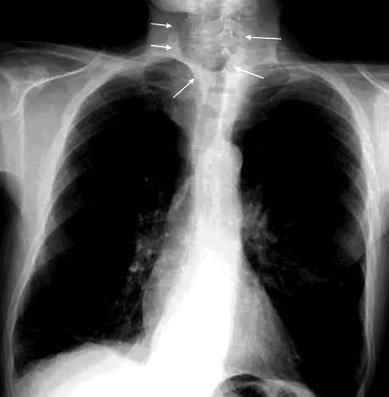

Pliegue axilar Normal

Rehúsa cirugía

2011. Acude por masa axilar

Linfoma NH de cél. B. Invasión Transtorácica.

Afectación axilar